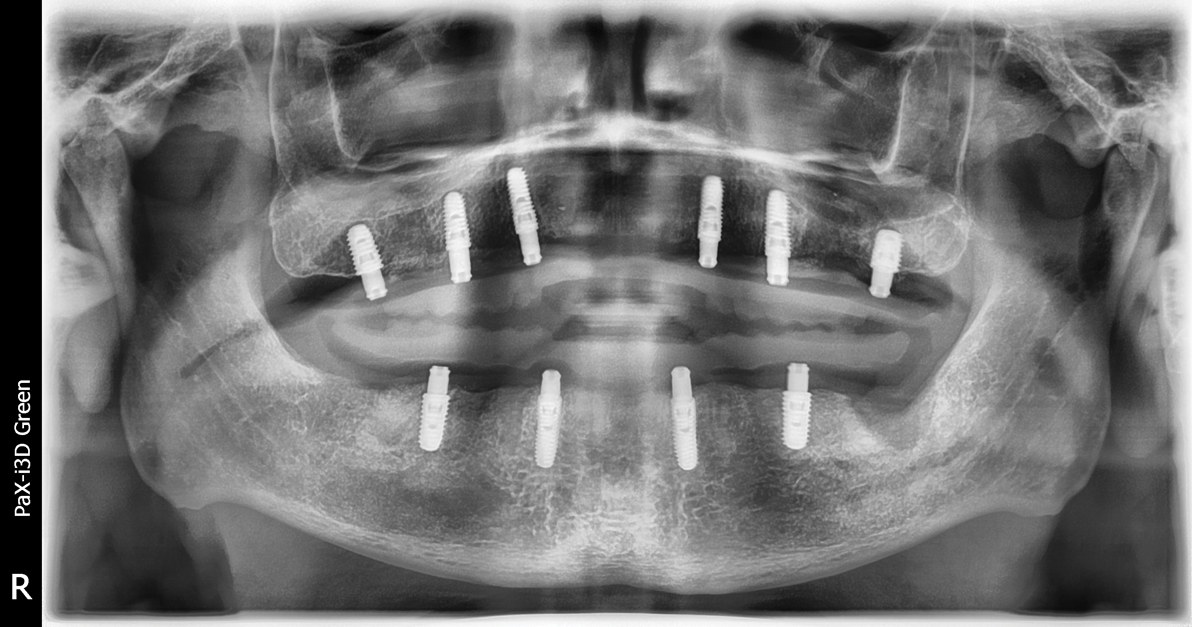

The patient returned and implants were assessed for integration and implant exposure procedures. A crestal incision was made and healing abutments were placed; at the time of uncovery, tissue measurements were made from the top of the implant platform to the superior portion of the tissues. Two weeks later, the patient returned and overdenture abutments (LOCATOR® R-Tx, Zest Dental Solutions, [alternatively: ERA, Sterngold; Hader, Preat]) in tissue heights corresponding to the measured tissue depths were placed (Figure 4 and Figure 5). After placement of the abutments, a panoramic radiograph was made to confirm complete adaptation of the abutments to the dental implants (Figure 6).Abutments were torqued to manufacturer's recommended torque values and denture housings were placed on top of each abutment (Figure 7). Optical scans of the maxillary and mandibular arches were made using the intraoral impression scanner. The patient's existing denture was relieved and relined with a silicone-based soft reline material (CHAIRSIDE® Soft, Zest Dental Solutions, [alternatively: Coe-Soft, GC America; Ufi Gel SC, Voco]). The intaglio and cameo surfaces of the maxillary and mandibular prostheses were optically scanned using the intraoral scanner.

Fig 6. Panoramic radiograph confirmed complete adaptation of the abutments to the implants prior to torquing the abutments.

Figure 6